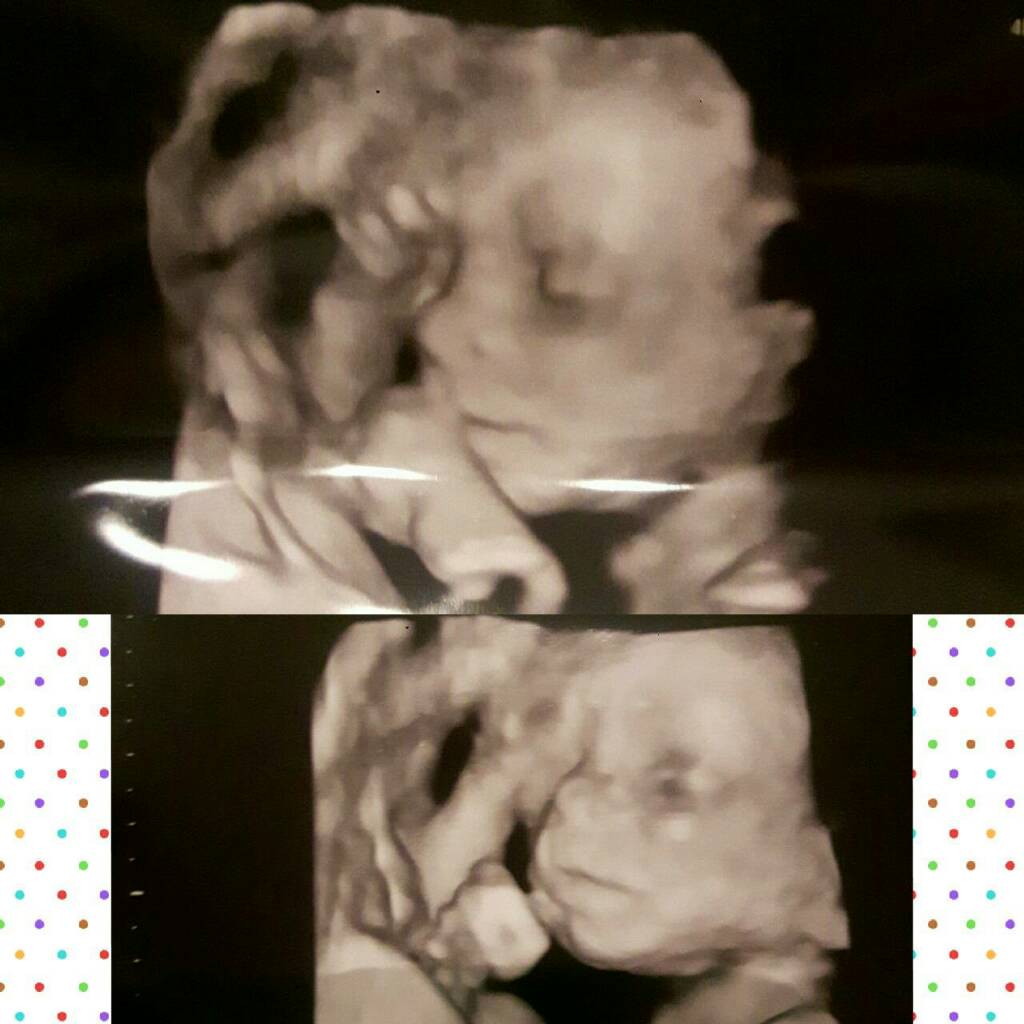

Mnie też rozczulają te zdjęcia 3d.Sandra napisała że zrobilo

Ja myślałam że to taka ściema ale zdjęcie mojego syneczke rozczula mnie do łez- widać autentycznie podobieństwo do mnie i do mojej córcia to przecież jeszcze takie maleństwo a już tak widać Zobacz załącznik 877214

Tym bardziej, że przy starszych dzieciach tego nie było.